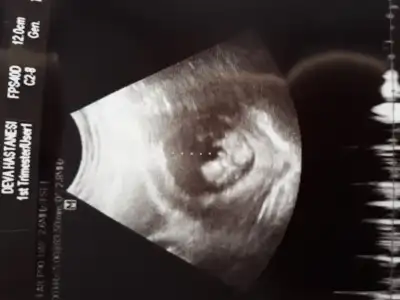

Usg 12 haftalık, doktorun tahmini 16 haftalıkKaç haftalıktı usg paylaştıgınız hatırlayamadım.dr kaçıncı haftada erkege benzetti![]()

Değişmeyebilir saglıkla gelsinUsg 12 haftalık, doktorun tahmini 16 haftalık![]()

12+1 canım:) doktor da erkek dedi bakalım net değil ama netleşince oy vercemNet olmamakla birlikte erkek diyorum kaç haftalık 11+ yada 12+ olmalı

Net olmamakla birlikte kız gibiOldu heralde kızlar 12+5 66 mm dedi tahmininiz nedir?

Net degil usg 12+ haftada paylaşın başka usg varsa paylaşın tahmin ederim

Kız gibi kafa şekli ama tutmaya bilirHaftaya tekrar gidicem onda 12 haftalik olcak , keske net olsaydi ya cok merak ediyom hele bidaha bakin![]()

Şimdilik erkek gibi 11 yada 12 hafta usg paylaşın daha net olur nubuHadi ya bu da mı erkek acaba bi erkek oğlu daha var da açıklanınca haber verirm artık teşekkürler canım ☺